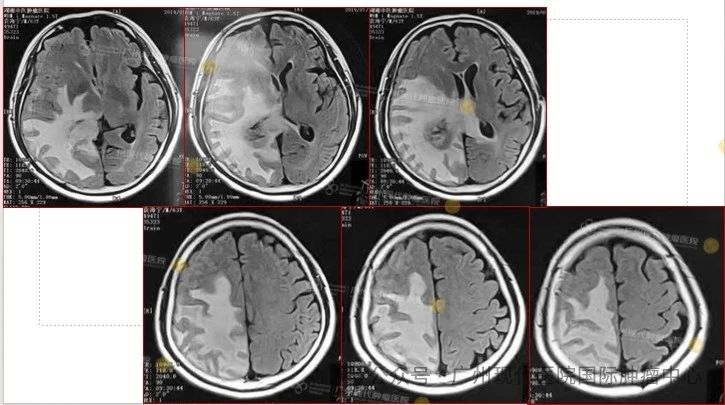

2019-7,颅内肿瘤基本消失,正常生活至今

2019年7月,颅内肿瘤已基本消失